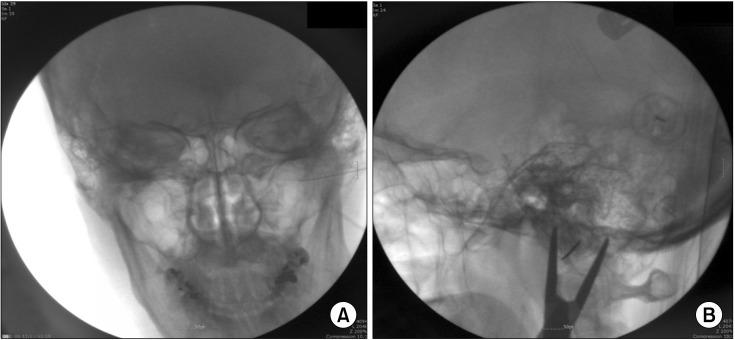

Hemifacial spasm is defined as unilateral, involuntary, irregular twitching of all or parts of the muscles innervated by facial nerves. Here, we present a case of recurrent hemifacial spasm after microvascular decompression (MVD) treated with pulsed radiofrequency (PRF) treatment with good results. A 35-year-old woman suffered from recurrent hemifacial spasm after MVD that was refractory to medical treatment and botulinum toxin injections. We attempted a left facial nerve block twice. Then, we applied PRF at a maximum temperature of 42℃ for 120 sec. Some response was observed, so we applied PRF two additional times. The frequency of twitch decreased from 3-4 Hz to < 0.5 Hz, and subjective severity on a visual analogue scale also decreased from 10/10 to 2-3/10. PRF treatment might be an effective medical treatment for refractory hemifacial spasm and has fewer complications and is less invasive compared with those of surgery.

面肌痉挛定义为面神经支配的肌肉出现单侧、不自主、不规则抽搐。在此,我们报告一例微血管减压术(MVD)后复发的面肌痉挛,采用脉冲射频(PRF)治疗效果良好。一位 35 岁女性,MVD 术后复发面肌痉挛,药物和肉毒毒素注射治疗均无效。我们尝试了两次左侧面神经阻滞,然后用 42°C 的最高温度进行 PRF 治疗 120 秒。观察到一些反应,因此又进行了两次 PRF 治疗。抽搐频率从 3-4Hz 降至<0.5Hz,视觉模拟评分的主观严重程度也从 10/10 降至 2-3/10。与手术相比,PRF 治疗可能是一种治疗难治性面肌痉挛的有效方法,其并发症更少,侵袭性更小。